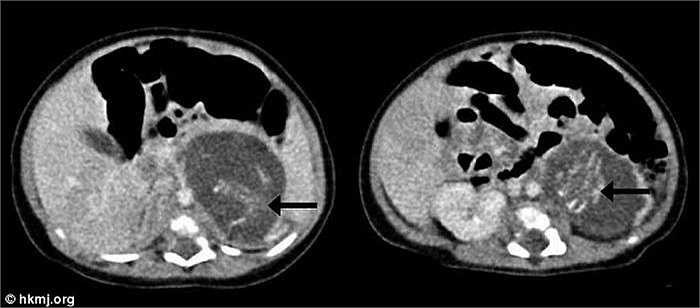

Mới đây, các bác sỹ Hồng Kông đã công bố một trường hợp bé gái mới chào đời với hai bào thai đang phát triển trong bụng.

Đây là hiện tượng ‘thai trong thai’ hay còn gọi là song sinh sống ký sinh do thụ tinh bên ngoài phôi - được xem là một trong những trường hợp y học rất hiếm trên thế giới.

Bé gái được sinh ra tại Bệnh viện Queen Elizabeth vào tháng 11/2010 đã trải qua cuộc phẫu thuật vào lúc 3 tuần tuổi để loại bỏ các bào thai.

Các bào thai từ 8-10 tuần tuổi. Mỗi thai nhi có 4 chi, 1 cột sống, xương sườn, ruột và hậu môn. Một thai nhi nặng 14,2 gram, thai nhi còn lại nặng 9,3 gram. Mỗi bào thai đều có dây rốn riêng nối với nhau thai.

Hiện tại, cô bé đã phục hồi tốt sau cuộc phẫu thuật và được xuất viện 8 ngày sau đó.

WHO xác nhận các bào thai này được xem là u phát triển đột biến, một dạng ung thư mà nguyên nhân được cho là do đa thai gây ra. Hiện tượng thai trong thai là một căn bệnh hiếm, có tỷ lệ xảy ra vào khoảng 1/500.000 ca. Tuy nhiên, thế giới mới chỉ ghi nhận chưa tới 200 ca.